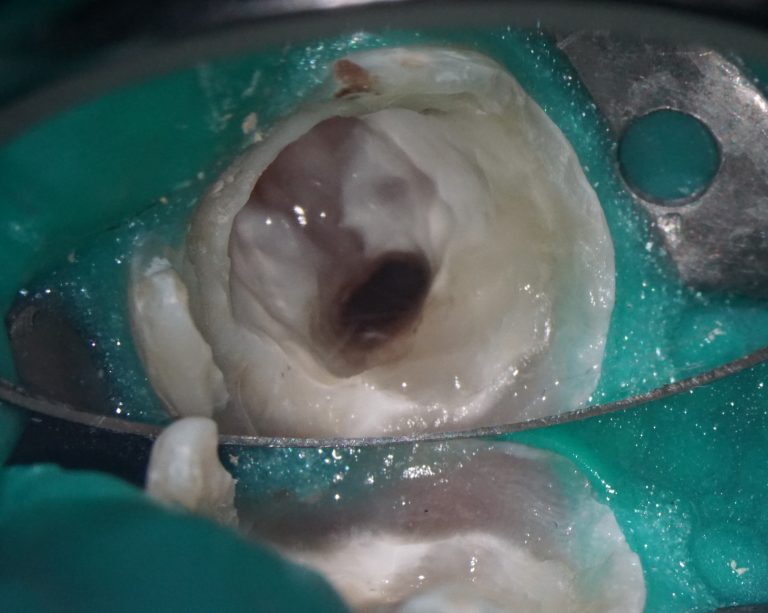

Solution: Diagnocat’s reports, based on CBCT and intraoral scans (STL files), help the clinician to quickly and accurately make decisions about treatment tactics and final tooth position, and to plan comprehensive treatment according to the individual needs of the patient